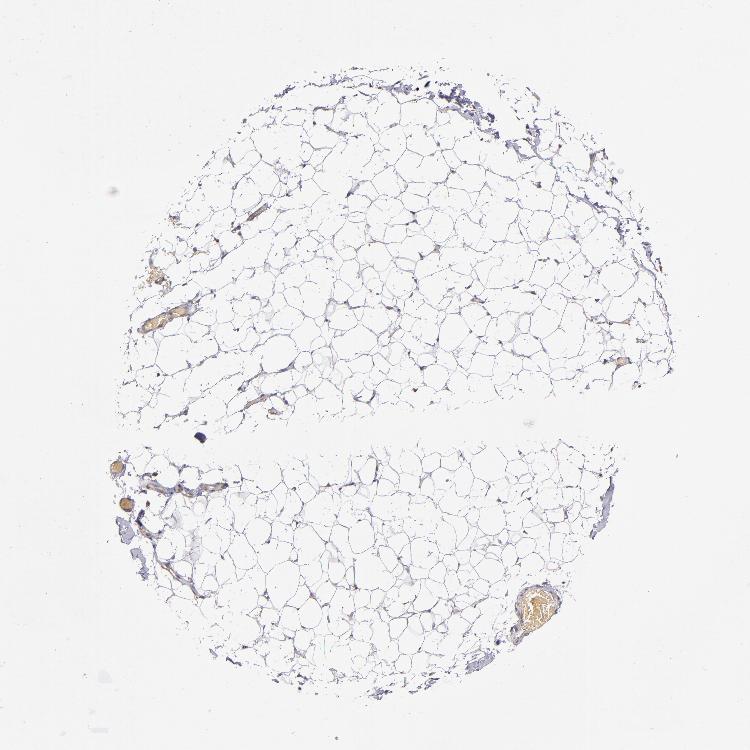

SOFT TISSUE 2 - Antibody stainingi

Antibody staining in the annotated cell types in the current human tissue is reported as not detected, low, medium, or high, based on conventional immunohistochemistry profiling in selected tissues. This score is based on the combination of the staining intensity and fraction of stained cells.

Each image is clickable and will lead to virtual microscopy that enables deeper exploration of all samples and also displays staining intensity scores, fraction scores and subcellular localization as well as patient and tissue information for each sample.

Antibody HPA001619Antibody HPA002078

Fibroblasts Not detectedMedium

Peripheral nerve Not detectedMedium